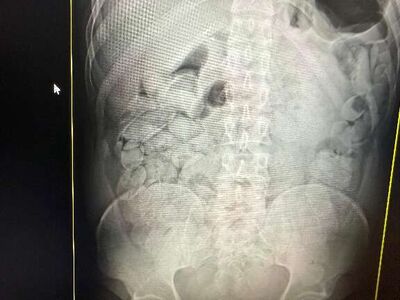

Bolivianos flagrados transportando cocaína ou derivados no estômago. Foto: Divulgação Bolivianos flagrados transportando cocaína ou derivados no estômago. Foto: Divulgação

Ao todo, 23 cidadãos bolivianos foram flagrados transportando cocaína ou derivados no estômago ou em mochilas, usando o transporte rodoviário como rota até São Paulo. A chamada “rota dos engolidores” sai da Bolívia, atravessa MS e segue para SP, explorando o corpo de quem tem muito pouco a perder.

Na operação de quarta-feira, dos 18 presos, 17 haviam engolido cápsulas de droga. Cada um ingeriu aproximadamente 100 cápsulas, totalizando cerca de 1,1 quilo por pessoa. Os 17 bolivianos, 14 homens e três mulheres, permanecerão sob custódia da Receita Federal no Pronto-Socorro Municipal por um período de um a três dias, até a completa eliminação das cápsulas. Após o procedimento, todos serão encaminhados à Polícia Federal para as providências legais.